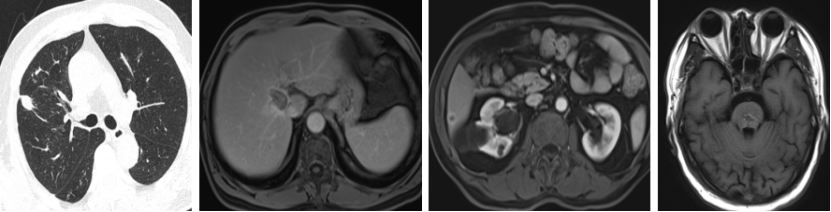

2020.5.28 复查示肝脏及脑干病灶稳定,肺部结节略增大。

2020.5.30至2021.5.25 行卡培他滨+贝伐珠单抗治疗,期间疗效评价SD。

2021.7.27 复查CT示右肺上叶近水平裂实性结节,较前稍增大;右肺前段沿肺纹理分布的多发结节,较前新发,疗效评价为PD。

2021.11.25 复查疗效评价为SD。

2022.3.29 复查:

1. 右肺上叶近水平裂实性结节,较前增大;

2. 右肺多发结节,部分较前略增大;

3. 肝右叶S8段异常强化灶,考虑转移性肿瘤,较前相仿;

4. 肝SVI段新发结节,考虑转移瘤;

5. 脑干转移瘤并周围水肿,较前增大。

2022.4.2 始行TAS-102+贝伐珠单抗(双周方案)治疗8个周期,6周期时复查,疗效评价为缩小的SD。